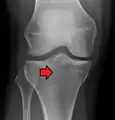

Subtle tibial plateau fracture on an AP X ray of the knee

In all injuries to the tibial plateau radiographs (commonly called x-rays) are imperative. Computed tomography scans are not always necessary but are sometimes critical for evaluating degree of fracture and determining a treatment plan that would not be possible with plain radiographs.[5] Magnetic Resonance images are the diagnostic modality of choice when meniscal, ligamentous and soft tissue injuries are suspected.[6][7] CT angiography should be considered if there is alteration of the distal pulses or concern about arterial injury.